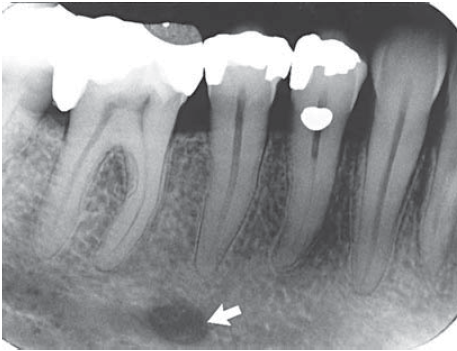

4. What is the anatomical structure indicated by arrow in this radiograph?